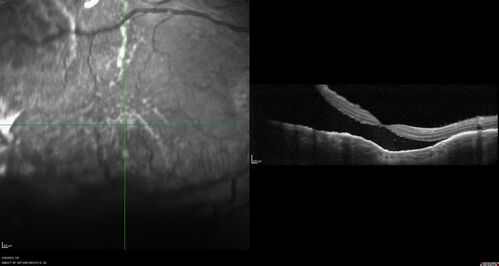

Choroidal Metastatic Breast Cancer with Exudative Detachment

58 year old female presented with 20/200 vision. Had 10 sessions of radiation and tumor shrank. The exudative detachment took almost a year to resolve. The vision improved to 20/40.